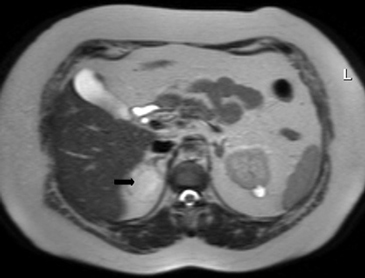

Los valores más utilizados son un 40% de lavado relativo de en fase tardía realizada a los 15 minutos y un lavado absoluto de 60%. De este modo cualquier lesión que muestre un lavado relativo mayor al 40% o absoluto mayor al 60% es consistente con un adenoma, con una sensibilidad y especificidad cercana al 100% (Figura 14 a, b y c). Dado la rapidez con que se obtiene un TAC de abdomen en la actualidad, algunos trabajos han recomendado utilizar cortes tardíos realizados a los 10 minutos, con el fin de optimizar el tiempo de examen, y utilizar un valor relativo de corte más conservador del 50%9.

A

B

C Figura 14. Tomografía computada de un adenoma suprarrenal izquierdo típico. Se ha colocado un circulo que representa la región de interés en la lesión de la glándula suprarrenal izquierda, obteniendo una medición promedio (Avg) expresada en unidades Hounsfield (UH). En fase precontraste (a) su densidad es de 0 UH, (flecha), en fase protovenosa (b) alcanza una densidad de 59 UH (cabeza de flecha), y en fase tardía (c) su lavado es de aproximadamente un 50%, llegando a una densidad de 30 UH.